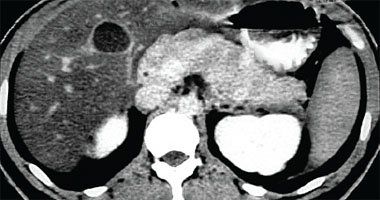

CT scan of the abdomen, axial section, showing pancreatic cancer. This scan was taken after an iodine injection and barium opacifi cation of the stomach.